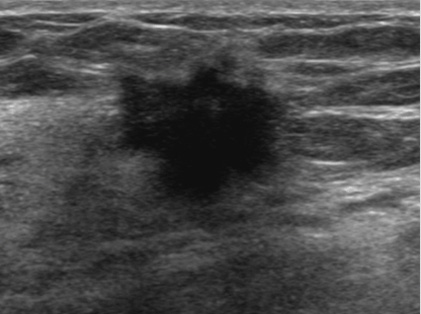

유방 초음파와 X-ray 검사

ㆍ유방 초음파 : 초음파를 이용하여 유방의 내부를 관찰하는 검사입니다. 유방을 압박하지 않고 검사할 수 있으며 통증이 없습니다. 또한, 유방의 모든 조직을 관찰할 수 있어 유방암의 조기 발견에 효과적입니다.

1) 모양 : 불규칙하거나 찌그러진 모양의 결절은 암일 가능성이 높습니다.

2) 경계 : 경계가 명확하지 않고 주변 조직과 침범하는 형태의 결절은 암일 가능성이 높습니다.